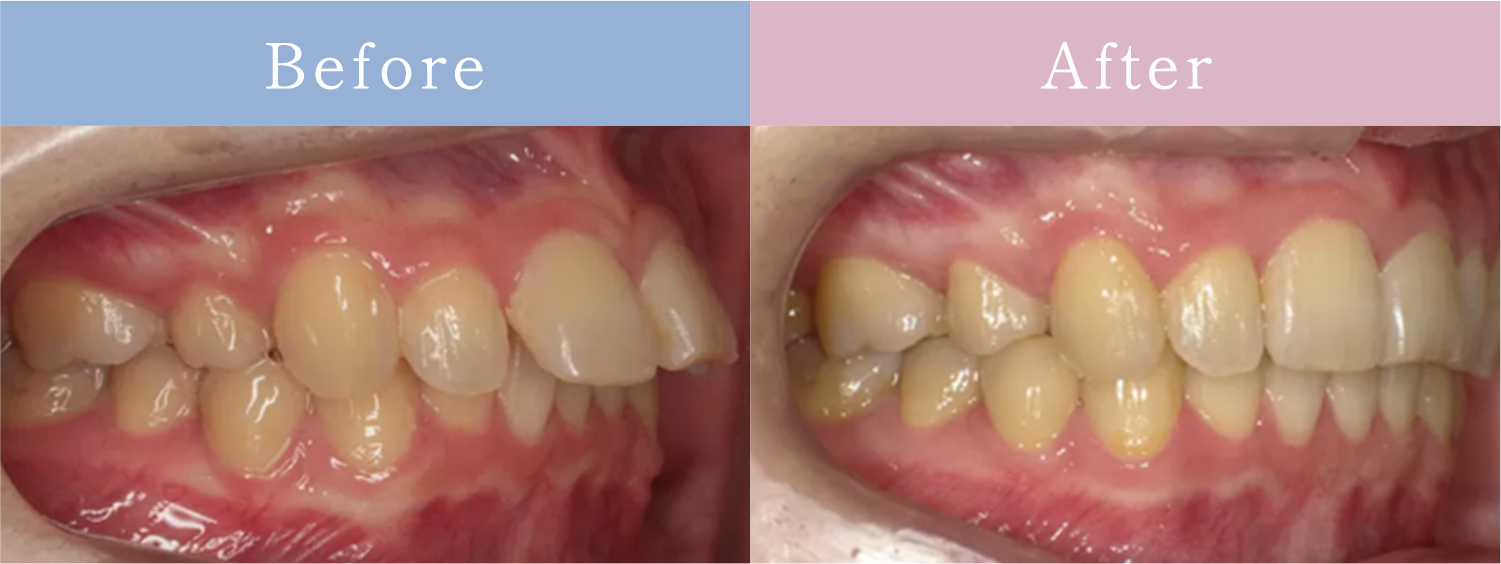

CASE症例

歯並びだけじゃない「お顔全体のバランスまで追求」

歯並びが原因でお顔立ちに

影響を与えている場合は

矯正治療で改善できます